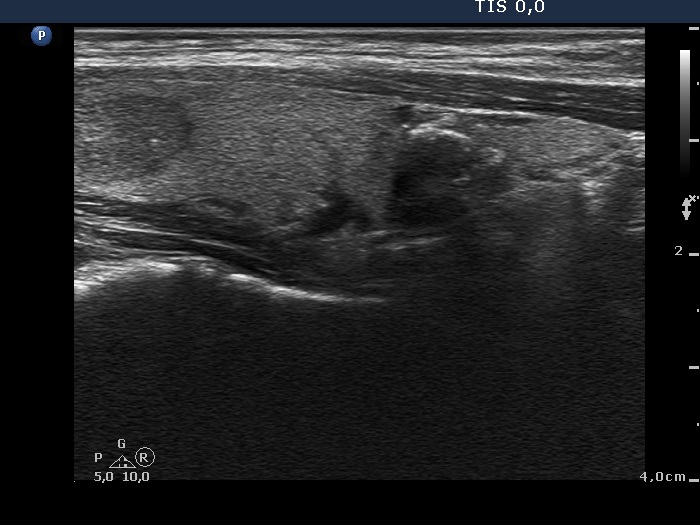

Benign hyperplastic nodule (histological diagnosis) - case cons037 |

Upper part of the right lobe |

|

The bright hyperechogenic granules (arrows) seem to be at first sight punctate echogenic foci. However, the presence of a few hyperechogenic lines (arrowheads) challenges this view: these figures might be presentations of a connective tissue.

Lower part of the right lobe

This nodule has multiple coarse calcifications and proliferation of a connective tissue (arrowheads and arrows).